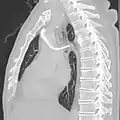

Vena azygos transportă sânge neoxigenat din pereții posteriori ai toracelui și abdomenului către vena cavă superioară. Anatomia acestui vas de sânge poate fi destul de variabilă. În unele cazuri rare, de exemplu, drenează și venele toracice, venele bronșice și chiar venele gonadelor. Vena este numită astfel, deoarece nu are venă simetric echivalentă pe partea stângă a corpului. Sistemul azygos este considerat a fi vena azygos situată de la coasta numărul 2 până la coasta numărul 4, în timp ce în partea stângă a corpului, vena hemiazygos și vena accesorie hemiazygos formează împreună sistemul venos analog. Vena azygos se formează prin unirea venelor lombare ascendente cu venele subcostale drepte la nivelul vertebrei toracice a XII-a, ascendent în mediastinul posterior și ajungând peste bronhia principală dreaptă, posterior la rădăcina plămânului drept pentru a se alătura venei cave superioare. Acest "arc al venei azygos" (arcus venae azygos) este un reper anatomic important. Ca o variație anatomică la 1-2% din populație, arcul poate fi deplasat lateral, creând astfel un sept pleural care separă un lob azygos de lobul superior al plămânului drept.

Anomaliile venei azygos pot fi observate pe radiografia toracică prin mărirea umbrei azygos la mai mult de 1 cm. Apariția fals pozitivă poate apărea în insuficiență cardiacă provocând presiuni crescute pe partea dreaptă a inimii sau limfadenopatie adiacentă. [7] Continuarea venei azygos și a venei hemiazygos către vena cavă inferioară nu este frecventă în viața de zi cu zi. Este foarte greu de observat, în special atunci când nu este asociat cu boli cardiace congenitale sau tromboză venoasă profundă. Astfel, este crucială diagnosticarea venei azygos lărgite la confluența cu vena cavă superioară și în spațiul retrocrural pentru a preveni diagnosticarea greșită ca masă paratraheală dreaptă. Pierderea segmentului intrahepatic al venei cave inferioare, cu continuarea venei azygos și a venei hemiazygos se întâmplă la 0,6% dintre pacienții diagnosticați pentru boală cardiacă congenitală și apare de obicei simultan cu situs inversus, asplenie sau polisplenie, vena cavă superioară stângă persistentă și sindromul venolobar pulmonar congenital. Continuarea venei azygos și a venei hemiazygos către vena cavă inferioară este rară, mai ales atunci când nu este asociat cu boli cardiace congenitale. [8]